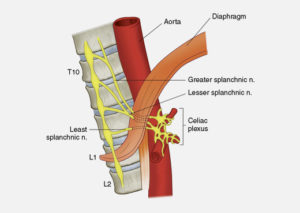

The splanchnic nerves communicate pain signals from the abdominal organs (stomach, small intestine, kidneys, gall bladder, liver, pancreas, spleen and adrenal gland) to the spinal cord where they continue on to the brain. Patients suffering from cancer-related abdominal pain, chronic pancreatitis or chronic abdominal pain (non-cancer) receive pain relief from a splanchnic nerve block.